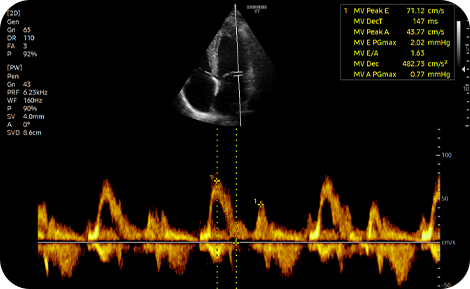

A semi-automated reporting

tool for heart diagnosis

HeartAssist™ while based on AI technology and through the measure button classifies views for heart diagnosis, selects measurement items, and provides results.

cardiac solutions : HeartAssist™